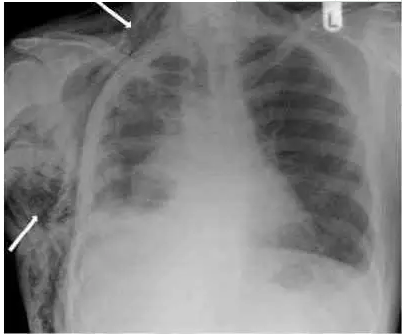

气胸的典型x线表现

气胸的典型x线表现,气胸的x线表现

气胸的x线表现

气胸的x线表现图片

典型气胸x线胸片图解

气胸胸片典型图片

气胸胸片典型图片x片

气胸x线胸片特征

气胸x线胸片

气胸x线胸片图解

气胸x线胸片报告

气胸胸片怎么看

气胸胸片图解

气胸胸片

气胸